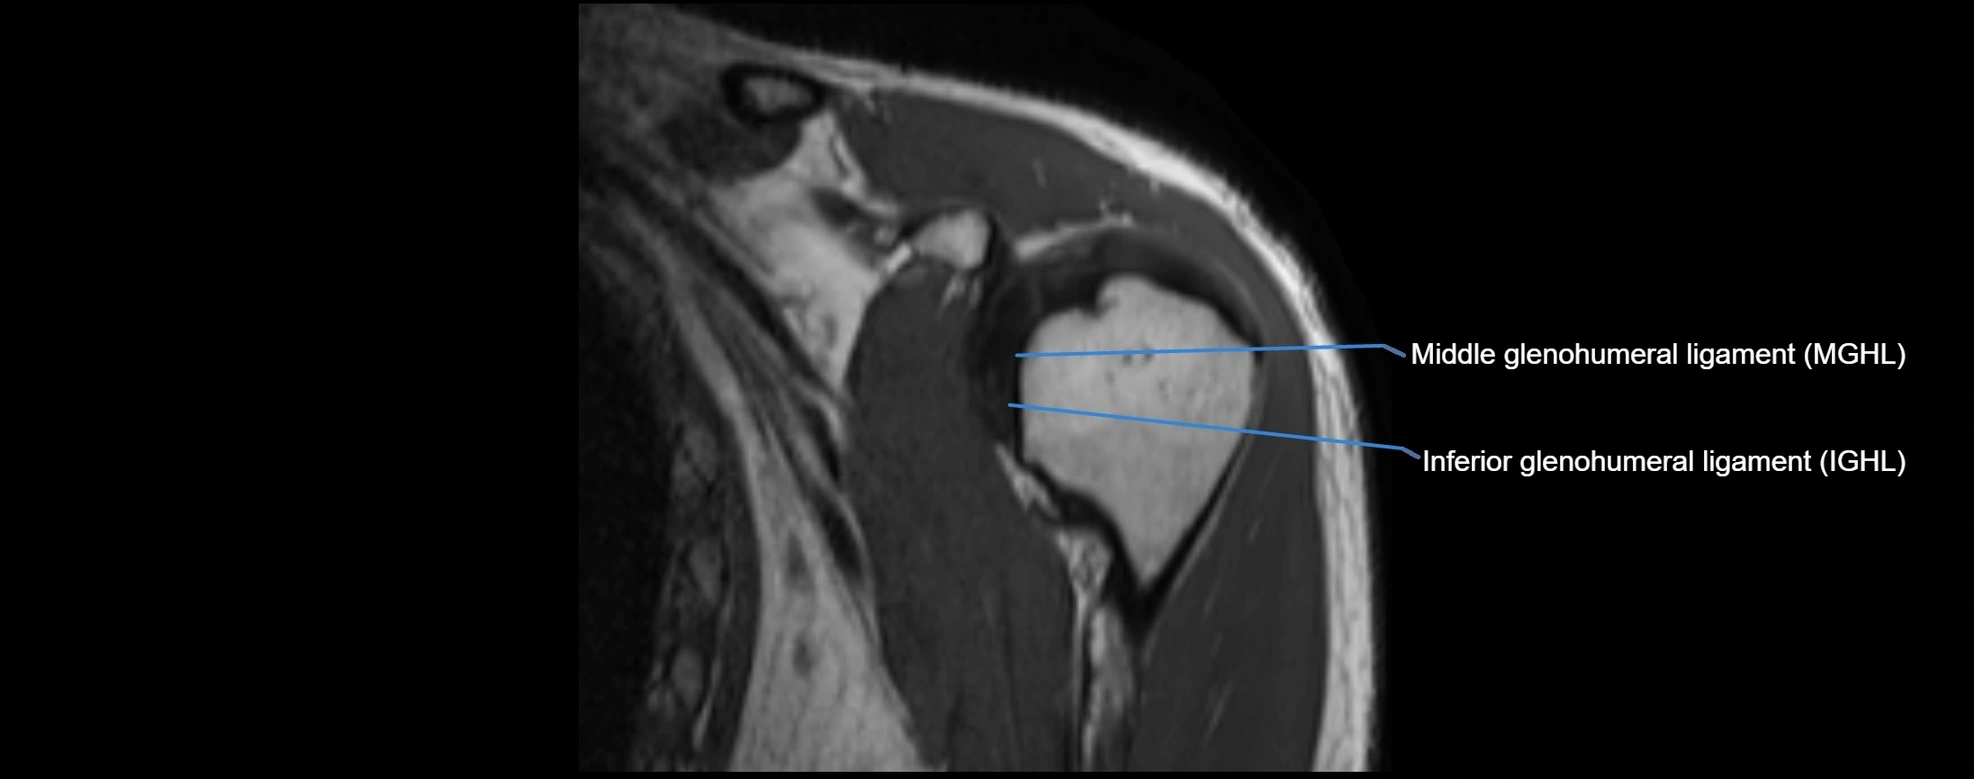

MRI Appearance

• T1-weighted images:

• Normal ligament: Low signal (dark linear band) spanning acromion to clavicle.

• T2-weighted images:

• Normal ligament: Low signal, homogeneous.

• Proton Density Fat-Saturated (PD FS):

• Normal ligament: Low signal, uniform thickness.

CT image

image